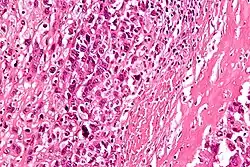

| Intermediate-magnification micrograph of an osteosarcoma (center and right of image) adjacent to non-malignant bone (left-bottom of image): The top-right of the image has poorly differentiated tumor. Osteoid with a high density of malignant cells is seen between the non-malignant bone and poorly differentiated tumor (H&E stain). | |

Microscopically: The characteristic feature of osteosarcoma is presence of osteoid (bone formation) within the tumor. Tumor cells are very pleomorphic (anaplastic), some are giant, numerous atypical mitoses. These cells produce osteoid describing irregular trabeculae (amorphous, eosinophilic/pink) with or without central calcification (hematoxylinophilic/blue, granular)—tumor bone. Tumor cells are included in the osteoid matrix. Depending on the features of the tumor cells present (whether they resemble bone cells, cartilage cells, or fibroblast cells), the tumor can be subclassified. Osteosarcomas may exhibit multinucleated osteoclast-like giant cells.[22]